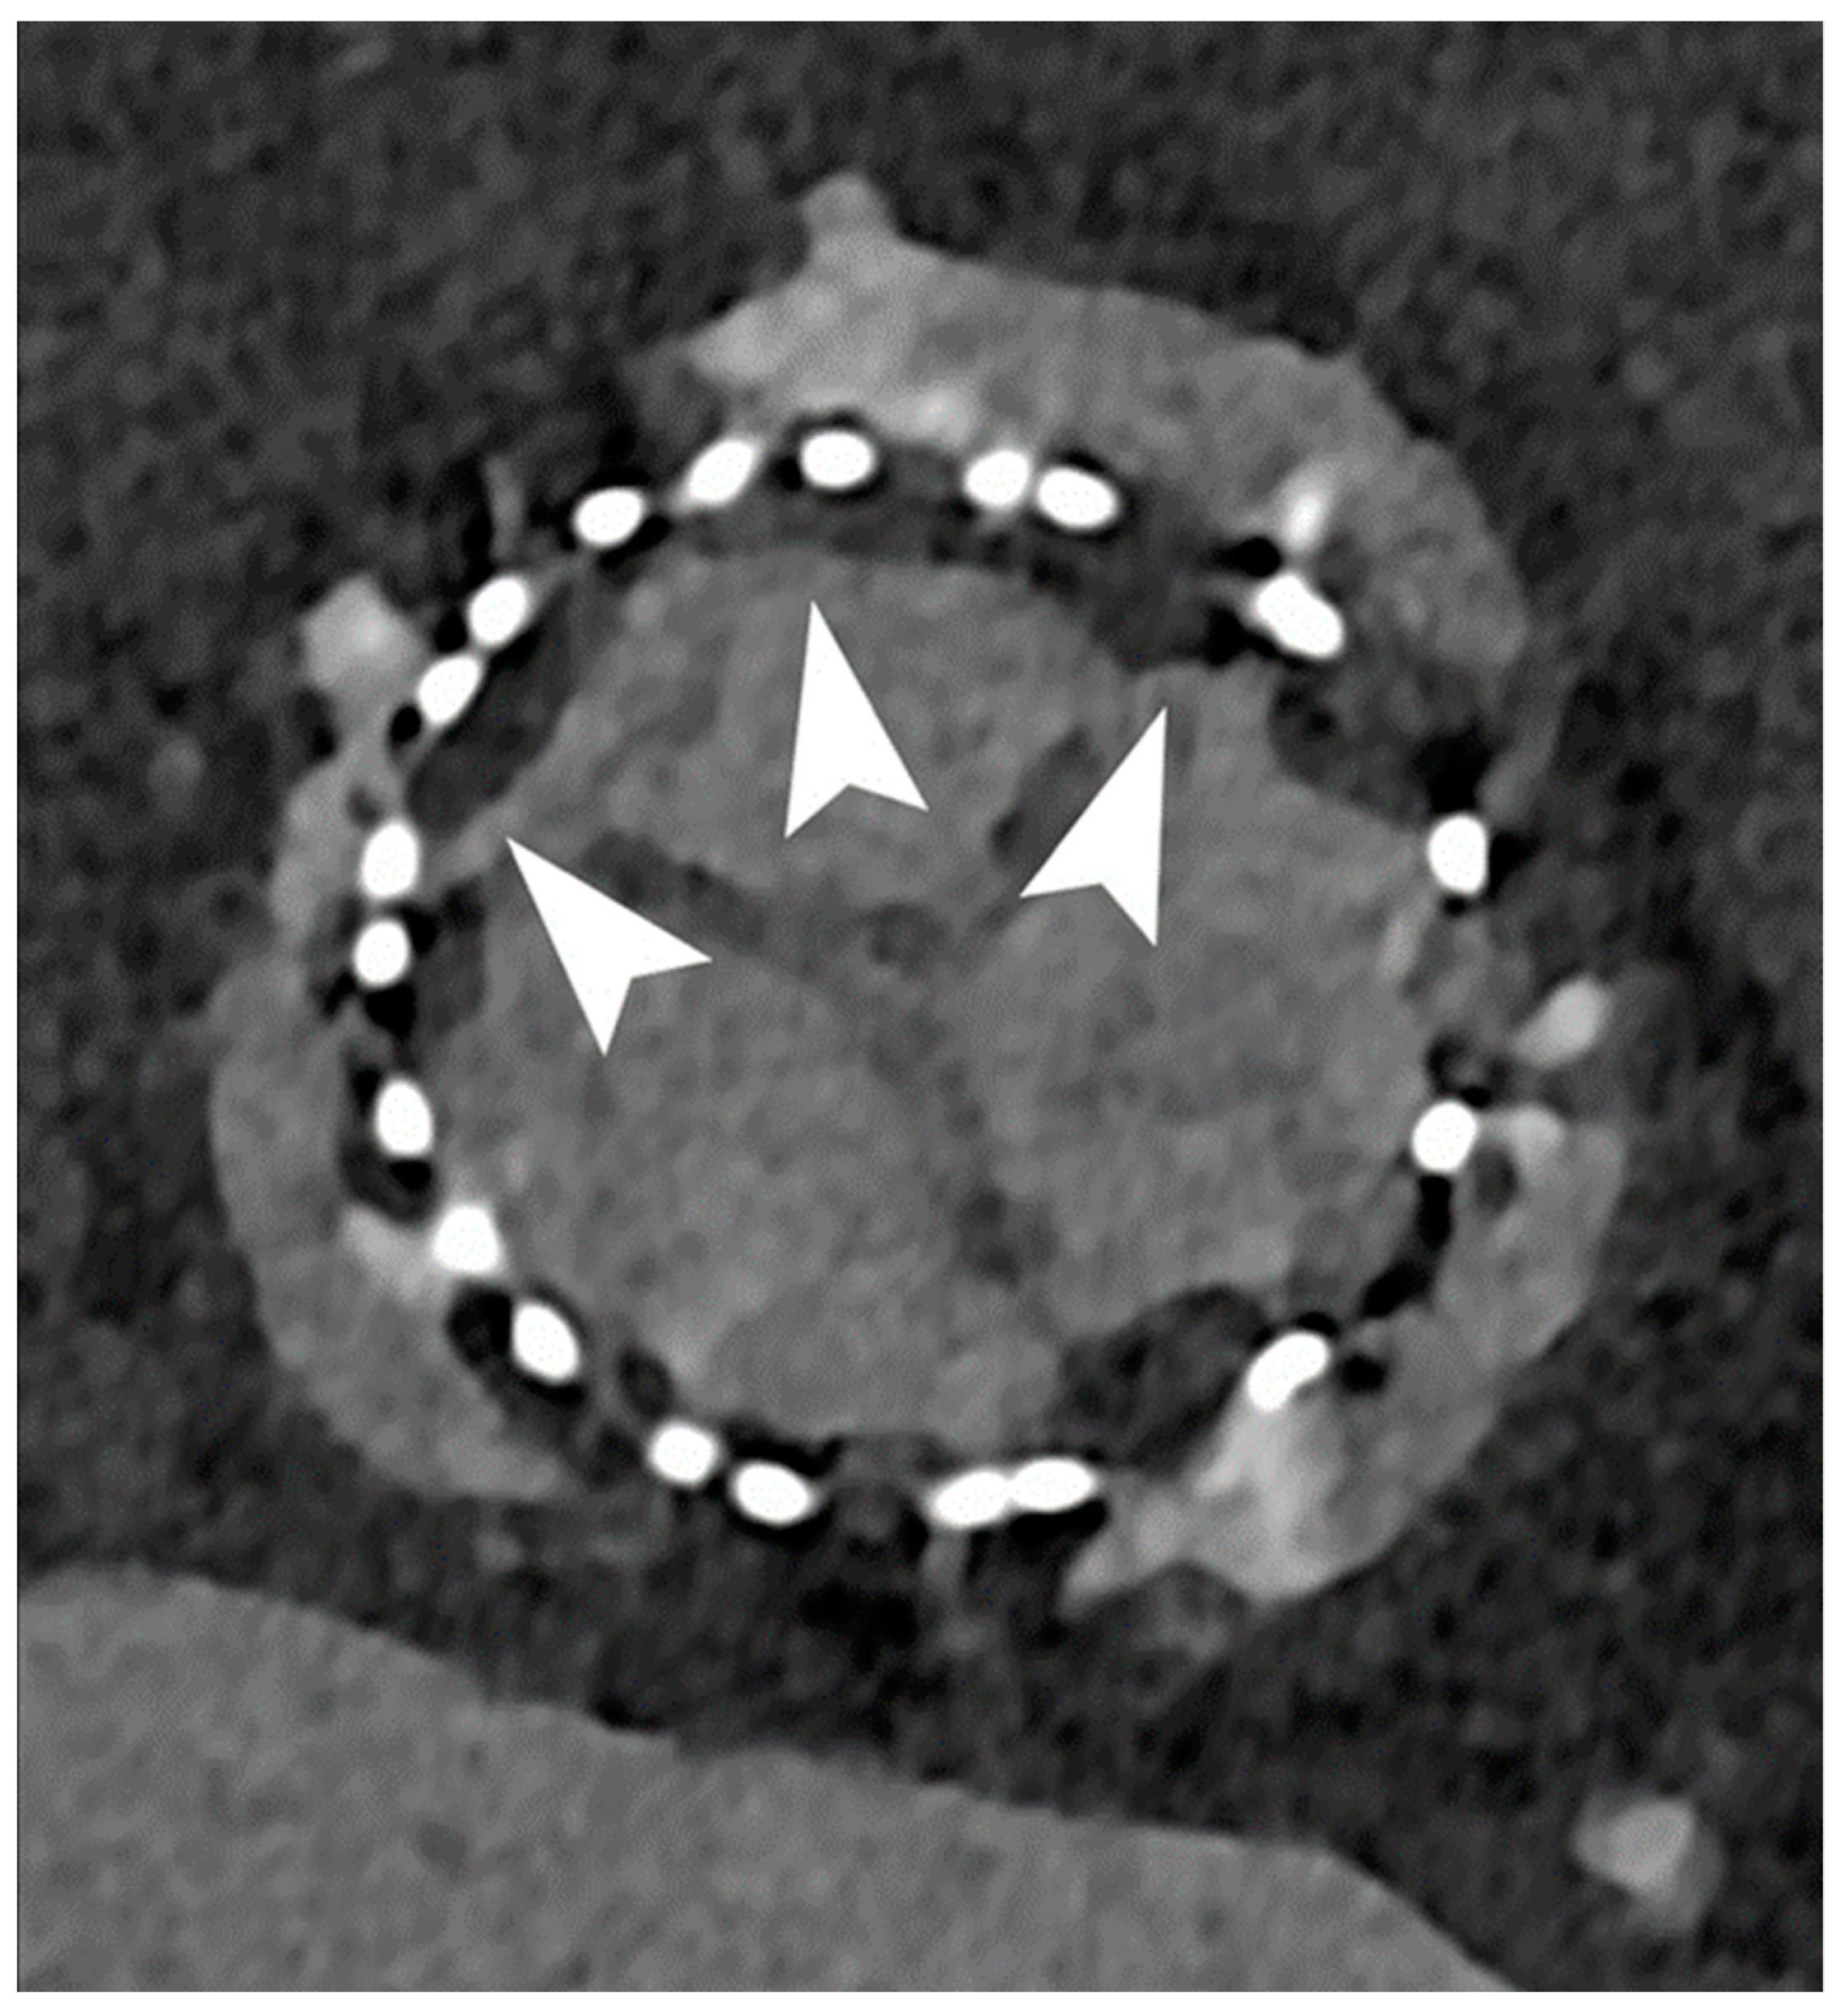

3.2. Coronary Stent

- Boccalini, S.; Si-Mohamed, S.A.; Lacombe, H.; Diaw, A.; Varasteh, M.; Rodesch, P.A.; Villien, M.; Sigovan, M.; Dessouky, R.; Coulon, P.; et al. First In-Human Results of Computed Tomography Angiography for Coronary Stent Assessment With a Spectral Photon Counting Computed Tomography. Invest. Radiol. 2022, 57, 212–221. [Google Scholar] [CrossRef] [PubMed]

- Symons, R.; De Bruecker, Y.; Roosen, J.; Van Camp, L.; Cork, T.E.; Kappler, S.; Ulzheimer, S.; Sandfort, V.; Bluemke, D.A.; Pourmorteza, A. Quarter-millimeter spectral coronary stent imaging with photon-counting CT: Initial experience. J. Cardiovasc. Comput. Tomogr. 2018, 12, 509–515. [Google Scholar] [CrossRef] [PubMed]

| Boccalini et al. [33] | 2022 | In vivo (human) | 8 | Coronary stent Dose reduction | Superior stent and lumen visibility with fewer blooming artifacts and lower dose radiation for PCCT versus conventional CT. |

| Mannil et al. [23] | 2018 | In vitro | Coronary stent | In comparison with EID-CT, PCCT offered superior in stent visibility, fewer blooming and partial volume artifacts, with a lower increase in the attenuation of the lumen inside the stent. | |

| Symons et al. [34] | 2018 | In vitro | Coronary stent | Better luminal depiction with lower image noise in PCCT compared to EID-CT. | |